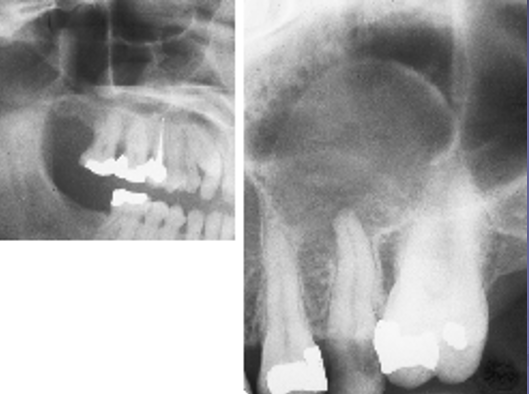

( in term of Radiology)

Appears as a dome shaped elevation of the floor of the sinus

Aneurysmal Bone Cyst

✎ A dome shape swelling on the floor of the sinus that’s associated with some _sort of inflammation of tooth of t_he premolar caused inflammation underneath the apex of the bone (right) and then that leads to accumulation of fluid which causes the sinus lining to elevate off the bone and fill with fluid

✎ After root canal therapy and once the infection gets under control, these will typically resolve on their own